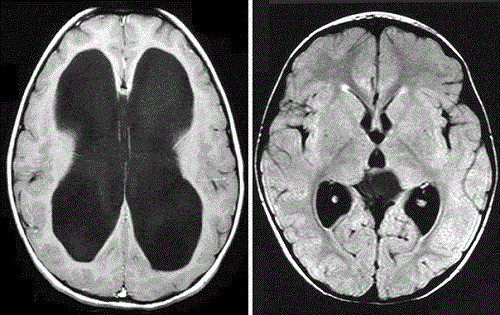

Giãn não thất là tình trạng não thất bên rộng hơn bình thường trên siêu âm. Trong thực hành thai nhi, bác sĩ thường đo ở tâm nhĩ não thất bên. Mốc bình thường là dưới 10 mm. Khi từ 10 mm trở lên, thai được xếp vào nhóm giãn não thất.

Giãn não thất là một mô tả hình ảnh. Nó cho biết khoang chứa dịch trong não đang rộng ra. Tuy nhiên, mô tả này chưa tự trả lời nguyên nhân là gì. Có trường hợp chỉ giãn nhẹ và đơn độc. Cũng có trường hợp đi kèm bất thường cấu trúc, di truyền hoặc nhiễm trùng.

Não úng thủy là tình trạng giãn hệ não thất do rối loạn lưu thông hoặc hấp thu dịch não tủy, thường kèm tăng áp lực trong hệ não thất. Nói cách khác, đây không chỉ là hình ảnh rộng ra. Đây là một quá trình bệnh lý có cơ chế phía sau. Trong bào thai, nguyên nhân có thể liên quan tắc nghẽn dòng chảy dịch não tủy, đặc biệt ở cống Sylvius, hoặc các bất thường cấu trúc khác.

Trong siêu âm thai, không thể đo trực tiếp áp lực não thất. Vì vậy, trên thực tế lâm sàng, hai thuật ngữ đôi khi bị dùng thay nhau. Dù vậy, nhiều tài liệu vẫn khuyến nghị gọi là giãn não thất khi đường kính 10–15 mm, và dùng não úng thủy khi giãn nặng trên 15 mm hoặc có bằng chứng gợi ý tắc nghẽn.

Khác nhau tiếp theo là ở mức độ. Giãn não thất thường chia làm ba nhóm. Mức nhẹ là 10 đến 12 mm. Mức vừa là 13 đến 15 mm. Mức nặng là trên 15 mm. Khi vượt 15 mm, nguy cơ bệnh lý nặng tăng rõ.

Bác sĩ sẽ nghĩ nhiều hơn đến não úng thủy khi não thất giãn nặng, đặc biệt trên 15 mm. Mức độ này làm tăng khả năng có tắc nghẽn lưu thông dịch não tủy hoặc tổn thương cấu trúc đáng kể. Ngoài ra, nếu giãn tăng dần qua các lần siêu âm, nguy cơ bệnh lý nền cũng cao hơn.